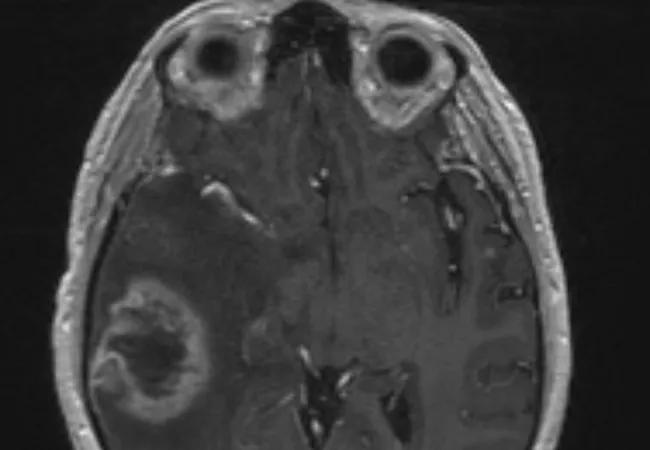

Oncologists often struggle to distinguish radiation-induced treatment effects from tumor recurrence in brain metastasis patients when looking at follow-up MRIs after radiosurgery.

Both conditions have similar morphological appearances on an MRI, and the patients can also exhibit similar symptoms: edema, memory loss, cognitive difficulties, seizures. The treatment for radiation necrosis (RN), however, is far less invasive than the treatment for tumor regrowth.

Because it is difficult to distinguish between tumor recurrence and RN on an MRI, as many as 20 to 40 percent of all patients are subjected to multiple radiological studies, brain lesion biopsies and even resections for what is ultimately deemed RN. Brain biopsy is currently the only definitive test to determine whether an MRI image is RN or tumor recurrence, but such procedures comes with a cost. Brain biopsies are risky, often causing morbidity and mortality.

Although both radiation necrosis and tumor recurrence appear similar on an MRI, studies have shown that the underlying biological pathways are fundamentally different. The researchers reasoned that there would be phenotypic differences that, while not easily seen by the human eye, could be found on MRIs and used to distinguish the two.

The program, which Tiwari’s group named Co-occurrence of Local Anisotropic Gradient Orientations or CoLlAGe, looks at the edges of each pixel in the image captured in an MRI to see if they point the same way or in different directions. The latter indicates chaos, the hallmark of a tumor and not RN.